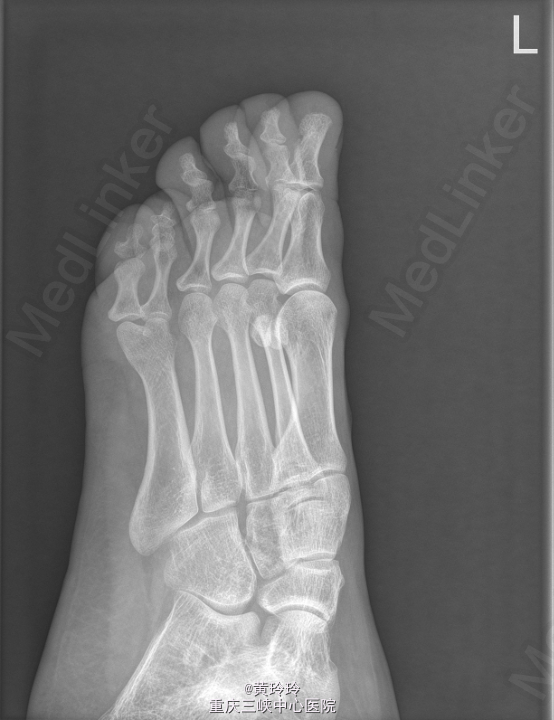

患者,女,32岁,因“ 发现左足多趾20年余 ”入院。

查体: 左足第四趾与第五趾之间长出一趾. X线提示左足第5多趾畸形。